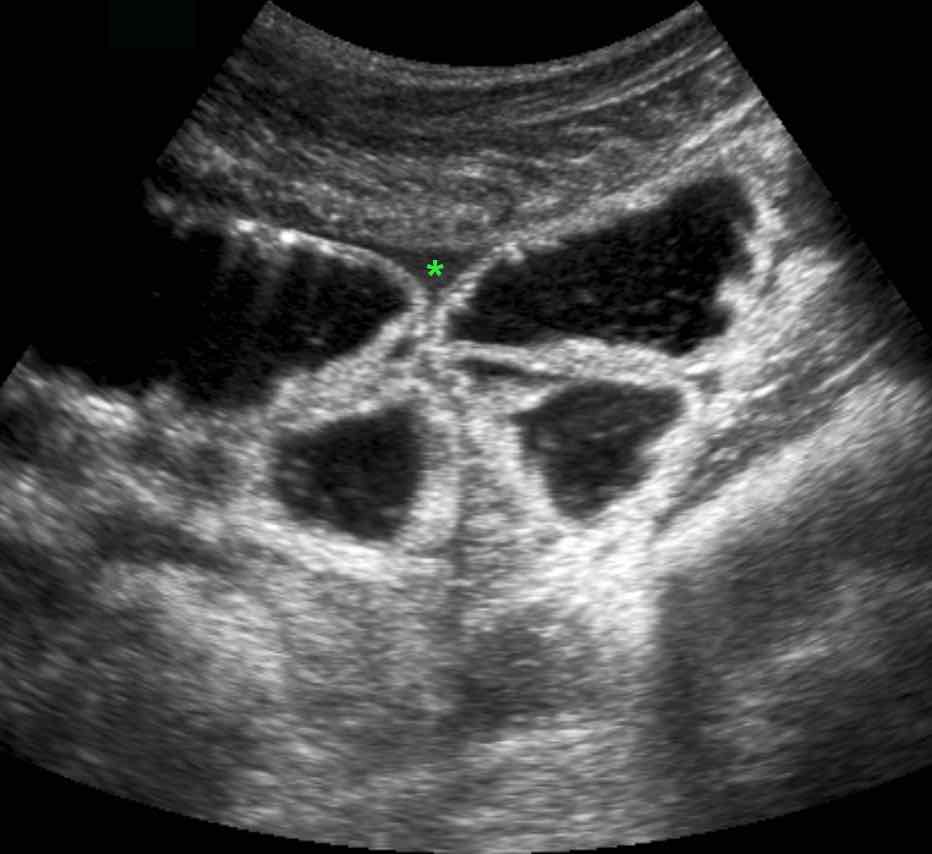

Ở bệnh nhân này, siêu âm cho thấy lượng lớn mô mỡ viêm (*) và hồi tràng dày thành, biểu hiện quá trình bao bọc thành công tình trạng thủng (sắp xảy ra) của ruột thừa (mũi tên).

Lưu ý sỏi phân vôi hóa (mũi tên trên CT) trong ruột thừa ở mức cao hơn.